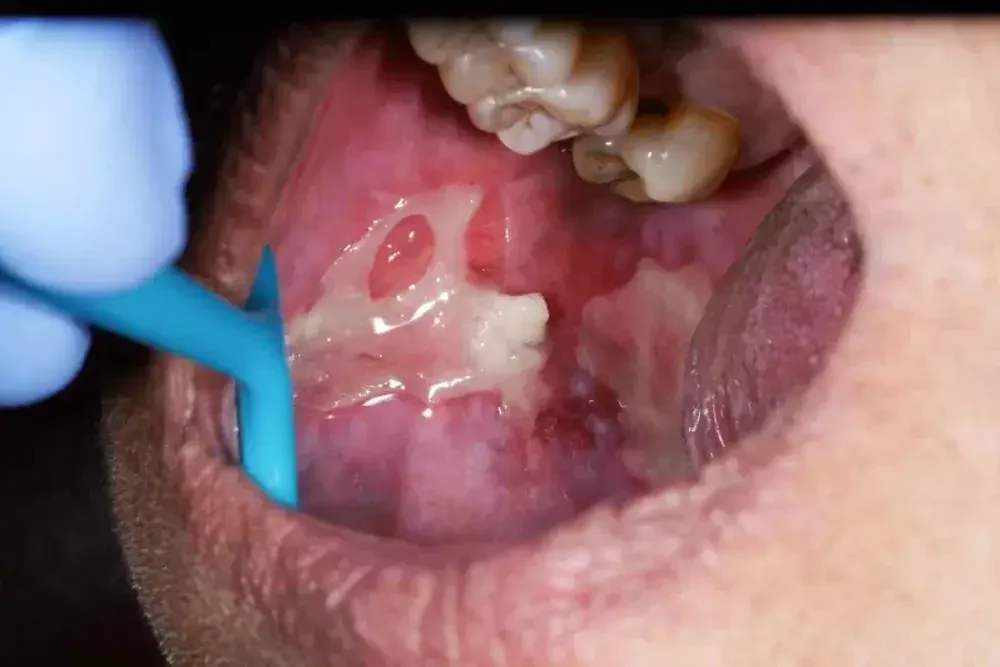

Bentuk luka sariawan di pipi dalam umumnya berbentuk bulat atau oval dengan tepi yang merah dan tengah berwarna putih atau kuning. Area ini termasuk bagian yang cukup sensitif, sehingga membuat penderita merasa sangat terganggu.

Benjolan atau Luka Terbuka Berwarna Putih atau Kuning dengan Pinggiran Merah

Gejala lainnya yang mudah dikenali adalah munculnya benjolan atau luka terbuka yang berwarna putih atau kekuningan di pipi bagian dalam.

Luka ini biasanya memiliki pinggiran merah yang menandakan adanya peradangan di sekitar area yang terluka. Benjolan atau luka ini bisa berbentuk bulat atau oval dan berukuran kecil, namun tetap memberikan rasa tidak nyaman saat berbicara atau makan.